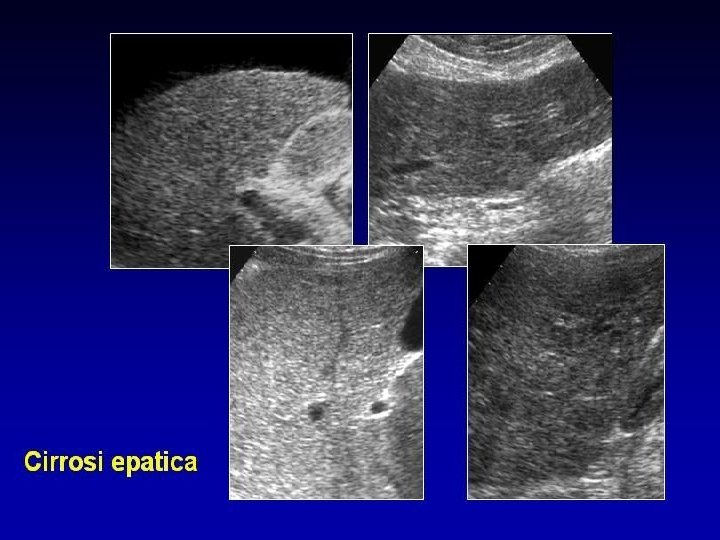

CIRROSI EPATICA La cirrosi epatica è una malattia cronica, diffusa del fegato, ad andamento lento e progressivo, caratterizzato da un'intensa fibrosi che trasforma la normale architettura epatica in noduli con una struttura anomala e con una conseguente perdita dei normali rapporti tra le cellule, i vasi sanguigni e le vie biliari. Rappresenta l'esito finale di numerose malattie del fegato che hanno in comune la capacità di causare la morte e la rigenerazione delle cellule epatiche e di innescare il processo dalla fibrosi.